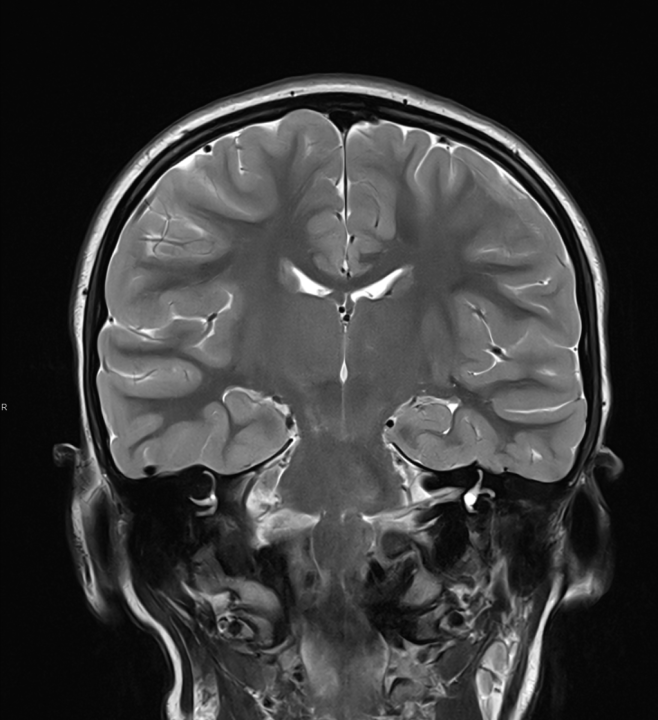

Tijekom Tjedna mozga Poliklinika Affidea Vita daje 20 posto popusta na magnetsku rezonancu!

Povodom obilježavanja Tjedna mozga od 11.

tjedan mozga

MR mozga

MR angiografija